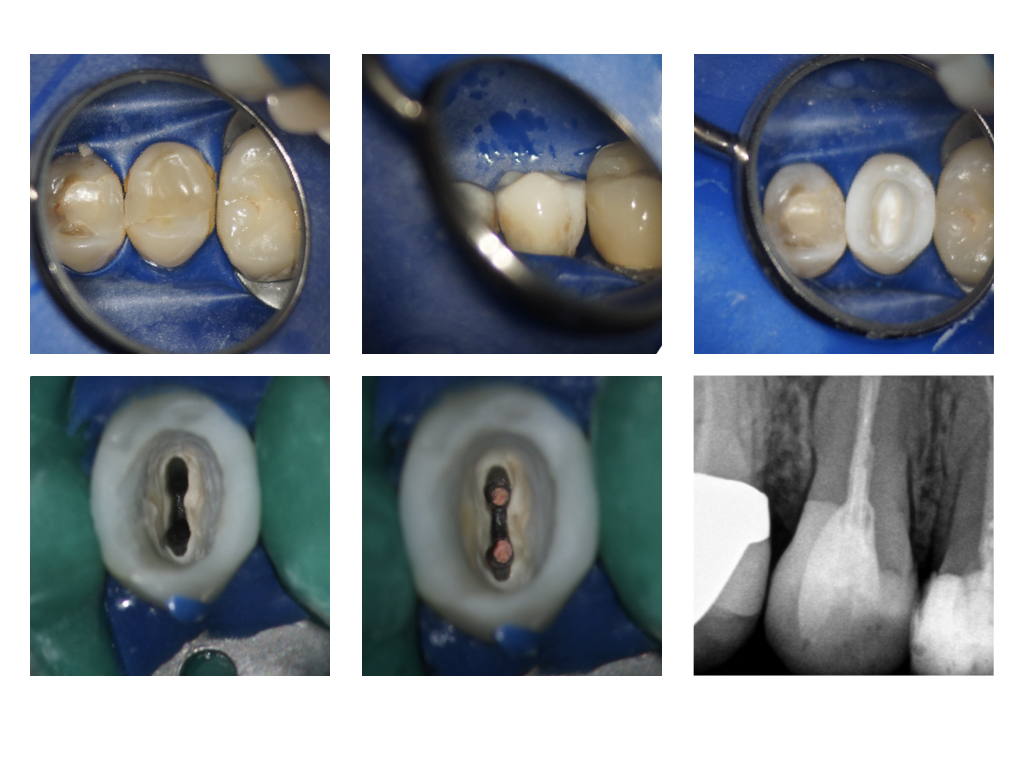

WS_Aufbau.024 Veröffentlicht 20. April 2017 am 1024 × 768 in Der präendodontische Aufbau in sequentieller Matritzentechnik